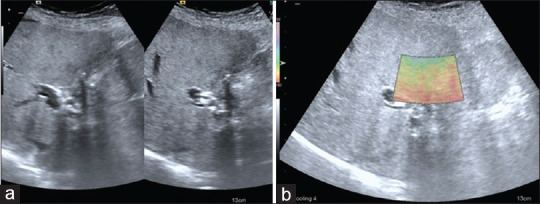

图 12

ADS III c 类患者(a)超声图像胆囊收缩且有结石 (b) VTI 图像上可见 E3 粘连。VTI:虚拟触摸成像